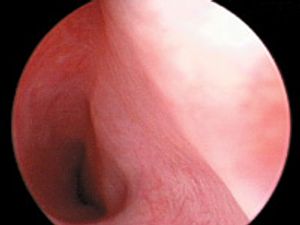

An 8-week-old 16.5-lb (7.5-kg) female Labrador retriever puppy was presented for evaluation of urinary incontinence. The puppy's incontinence had been present since the owner obtained the puppy at 4 weeks of age.